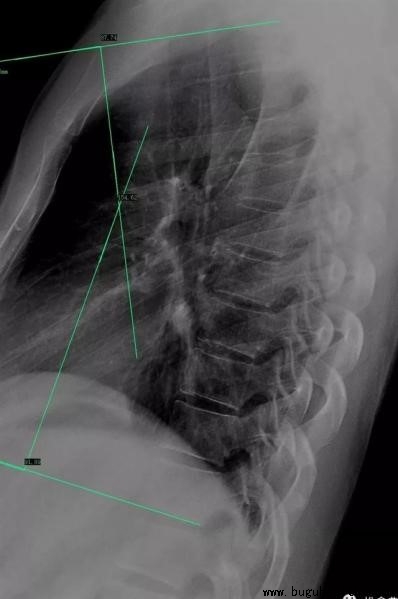

胸椎:正常的胸椎曲度主要由T1~T12胸椎形成,并以T6~T7椎体作为顶点,另外通过T2椎体上缘和T11椎体下缘分别做一切线,形成一夹角,正常范围是20°~50°。胸曲大于50°也就是胸曲过大,也就是临床见到的“驼背”情况。这其中主要出现2种类型的曲度改变,一种为胸段后凸,另一种则为胸腰段后凸。胸段后凸较为常见,常涉及T2~T12节段,顶椎常位于T6~T8节段。胸腰段后凸相对较少,常涉及T5~L4节段,顶椎常位于胸腰交界区附近。

脊柱侧弯矫正